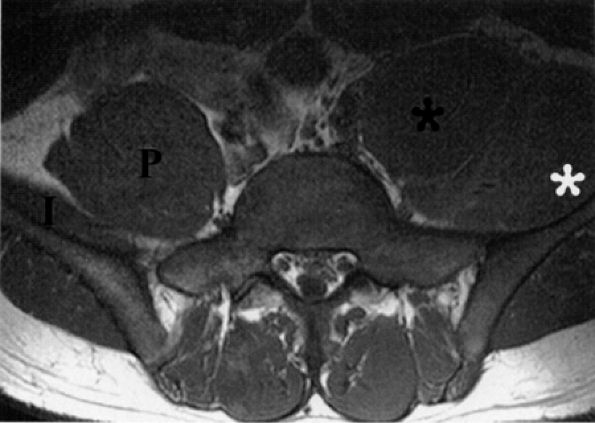

|

FIGURE 6.22 ● Femoral neuropathy secondary to sports-related iliacus muscle tear. Axial T1-weighted image demonstrating enlargement of the left iliac (white asterisk) and psoas muscles (black asterisk). The anteriorly displaced femoral nerve is not visualized. Compare with the right normal iliac (I) and psoas (P) muscles.